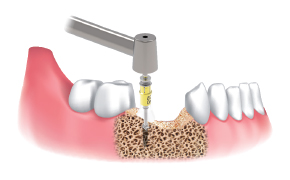

Secuencia de obtención :

Sitio de implante utilizando Ø3.5/4.0

Fresa de recolección con escudo de silicona.

Fresa punta para marcar sitio de obtención y de implante.

Seleccionar fresa Ø3.5/4.0 e insertar el stopper en la fresa seleccionada. Luego poner la pantalla en el stopper Ø3.5&4.0.

Fresar entre 300 a 500 RPM con irrigación y obtener las limallas de hueso.